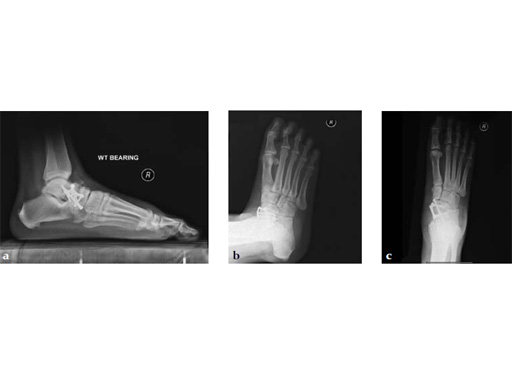

Case 2: First MTP fusion plate

A 38-year-old man presented for opinion after two attempts to fuse the big toe MTP joint. The AP view is significant for luscency at the joint line. The lateral view is notable for loosening of the hardware and malposition because of the dorsiflexion built in to the precontoured implant. Revision was planned using a 0 variable angle locking/compression hallux MTP plate.

At 10 weeks postoperatively (see Fig. 2ab) the patient had no pain with weight bearing. The lateral view demonstrates improved position of the toe using a 0angle plate.